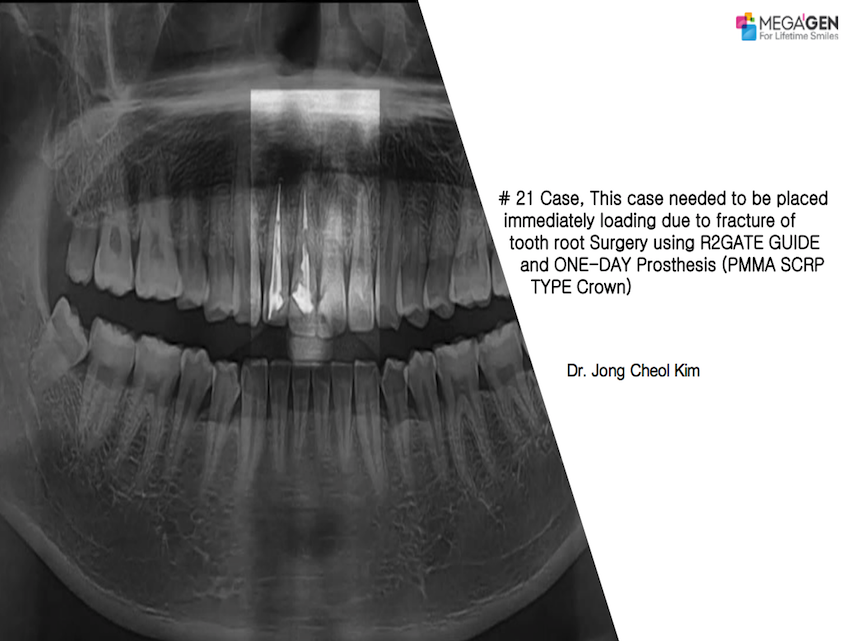

1 19 20 21 22 23 29